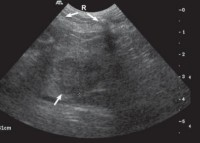

Hình 4.15. Hình ảnh xơ gan (mũi tên) | |